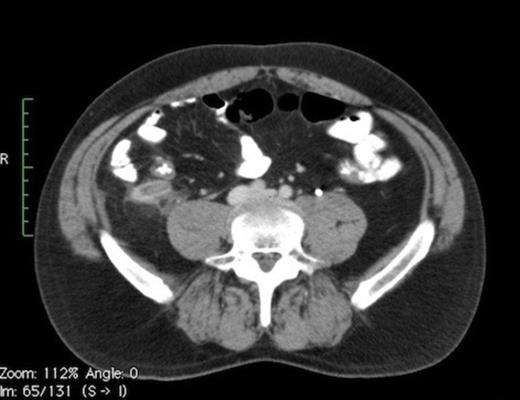

Contrast CT (Fig. 1A) depicts a thickened appendix measuring >12mm with periappendiceal fluid suggestive of acute appendicitis. Moderate hydronephrosis (Fig. 1C) of right kidney was noted with a 6mm calculus (Fig. 1B) in the right mid ureter.